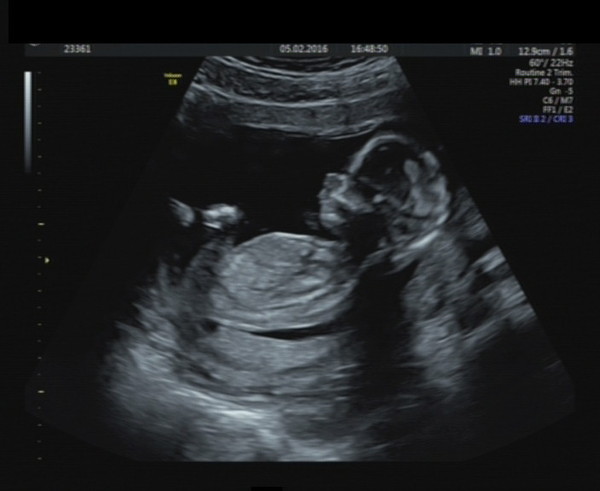

Had a scan today and everything looks good. The Birth Conpany were excellent, we had a lovely helpful sonographer. Attached a picture of the little one.

Lovely pic thom X

Great pic Thom

Lovely scan pics Thom and Becks.

Lovely scan photos becks and Thom I will be nearly 22 wks at mine so it's really tempting to get a private one especially after seeing the great photos

On a happier note what a beautiful scan picture ThomSmile